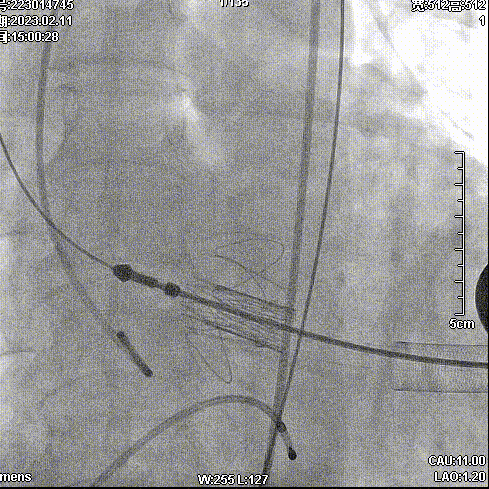

2月11日,新疆维吾尔自治区人民医院杨毅宁教授团队成功应用J-Valve完成两例具有挑战性的横位心TAVR病例。其中一例为窦部扩张+横位心,另外一例为升主动脉增宽+横位心,且两例患者均为主动脉瓣关闭不全(反流)。

病例二:升主增宽+横位心

病史简介:66岁男性,主因间断胸闷气短3年余,加重1周入院。

手术步骤

拔除股动脉血管鞘,缝合股动脉。手术顺利结束。